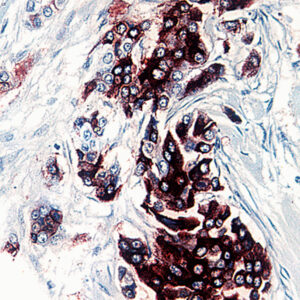

Anti-YAP

YAP encodes a nuclear effector of the Hippo signaling pathway which plays a pivotal role in regulating tissue growth and organ size. Deregulation of the Hippo pathway causes tumor formation and malignancy and hence, YAP may function as a potential target for cancer treatment. YAP is expressed at high levels in the lung, placenta, prostate, testis and ovary.

| Tissue Type/Cancer Type | Breast Carcinoma Tissue |